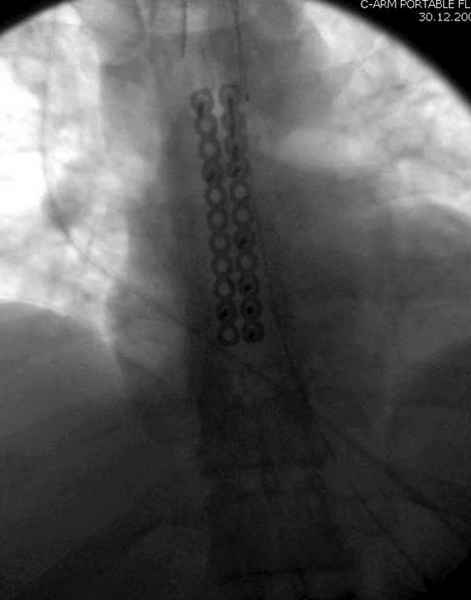

Юра, интересно, насколько такой остеосинтез контролирует степень репозиции, а то у меня имеются снимки девочки 11 лет, направленной ко мне на консультацию из одной из республик бывшего союза.

После торакальной операции, по-видимому, сильно натянули проволоку, и в результате получился захлест отломков в друг друга.

А простые посттравматические ложные суставы грудины приходилось оперировать с ограничителем сверла и с фиксацией 2.4 мм пластинами с угловой стабильностью.